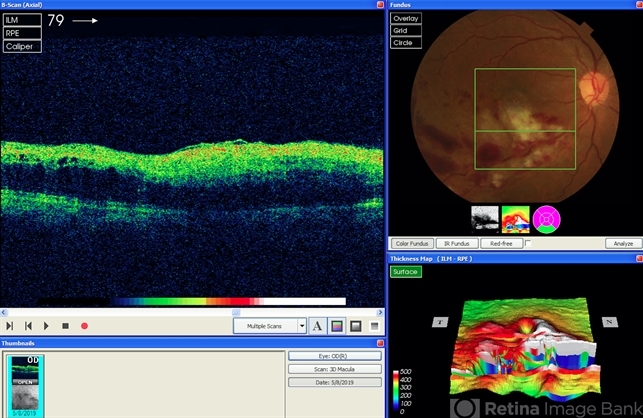

- branch retinal artery occlusion (BRAO), branch retinal vein occlusion (BRVO)

Optical coherence tomography system

Topcon 3D OCT - Description

- OCT of macula shows disorganization in the outer retinal layers.